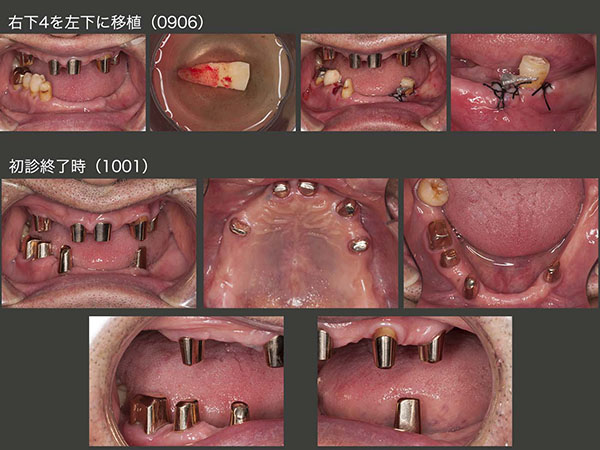

先に上顎のコーヌス義歯を製作した.つぎに下顎の義歯に取りかかったが,左下に歯がないためどうしても右咬みになっているのを何とか改善したいと考えた.最初左下にインプラントを1本植立したが,私の手技の稚拙のため生着しなかった.そこで,右下には歯が5本あることから,対合歯との接触が少なく,また抜歯しやすい小臼歯の右下4をドナー歯に選定し,2009年6月,左側に移植した.

下に示すスライドは,10年1月初診終了時の状態である.歯周ポケットは右下6を除いて3mm以下に改善した.